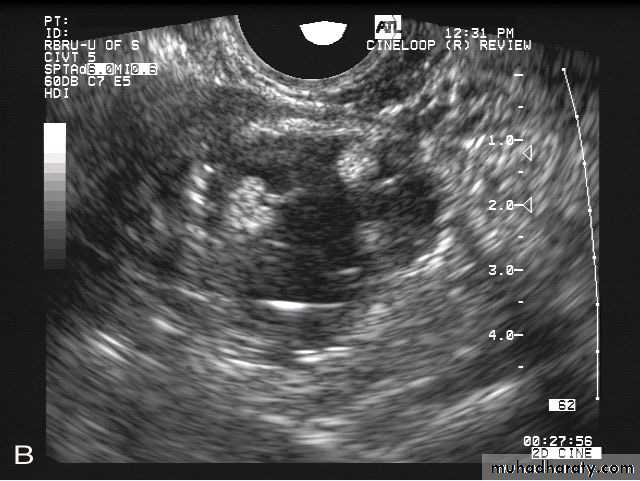

POLYCYSTIC OVARY SYNDROME

Ultrasonography in Gynaecology

Images from women with differing expressions of the four major subtypes of the metabolic syndrome associated with polycystic ovary syndrome (A–D). The images exhibit quite differing ultrasonographic appearances in the size and distribution of follicles within PCOS ovaries. A recent corpus luteum is clearly visible in the ovary in panel (D).

• POLYCYSTIC OVARY SYNDROME